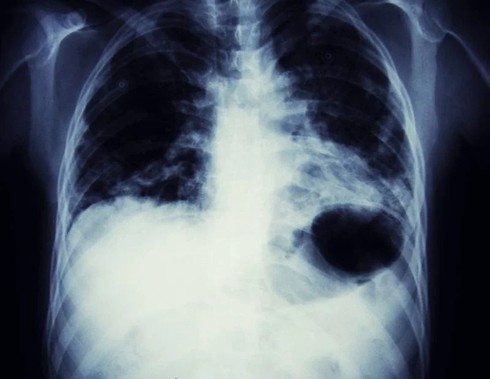

Bệnh lao:Lao là một bệnh hô hấp có tính lây truyền cao thông qua ho và hắt xì. Bệnh này tạo các vết thương trên mô phổi, các vết thương này lại tổn thương mạch máu, khiến người bệnh ho ra các cục máu đông |